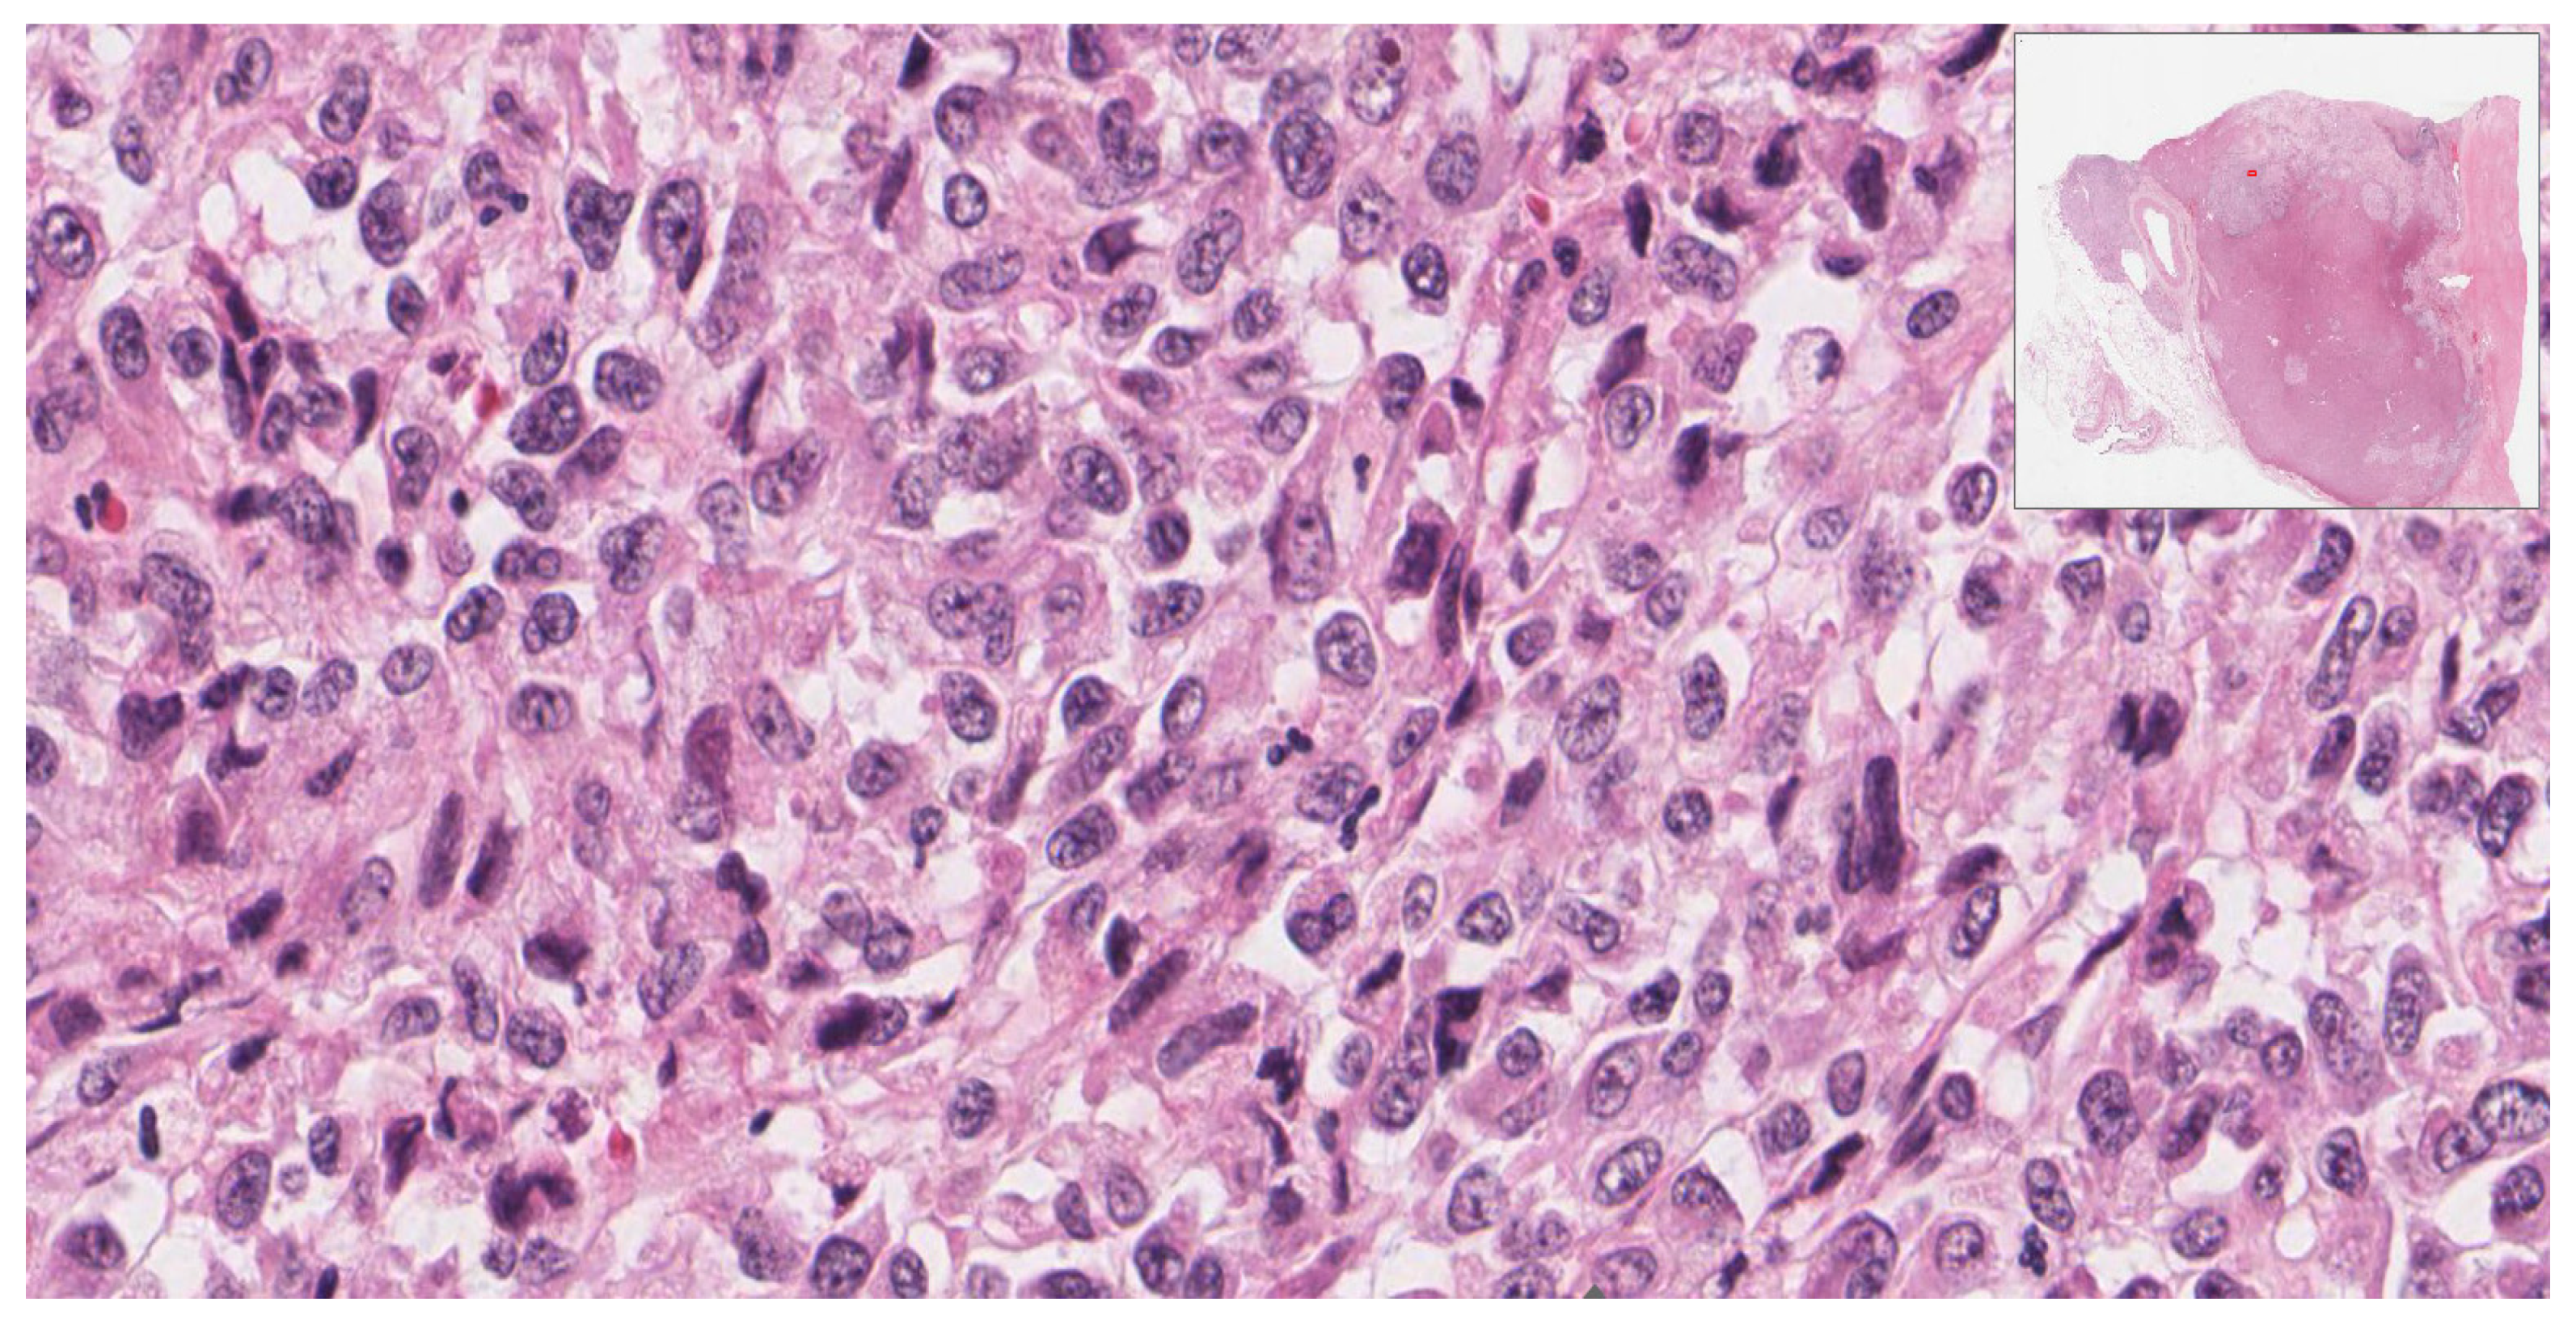

| Stain | Carcinomatous Component | Sarcomatous Component | Company | Clone |

|---|---|---|---|---|

| Calretinin | Positive | Negative | Ventana | SP65 |

| HMB-45 | Negative | Negative | Ventana | HMB-65 |

| Inhibin Alpha | Positive | Negative | Ventana | R1 |

| Synaptophysin | Positive | Negative | Ventana | SP11 |

| Myogenin | Negative | Negative | Ventana | F5D |

| Vimentin | Negative | Positive | Ventana | Vim 3B4 |

| Desmin | Negative | Positive | Ventana | DE-R-11 |

| Pax8 | Negative | Negative | Ventana | MRQ-50 |

| Pan-keratin | Negative | Negative | Ventana | AE1/AE3/PCK 26 |